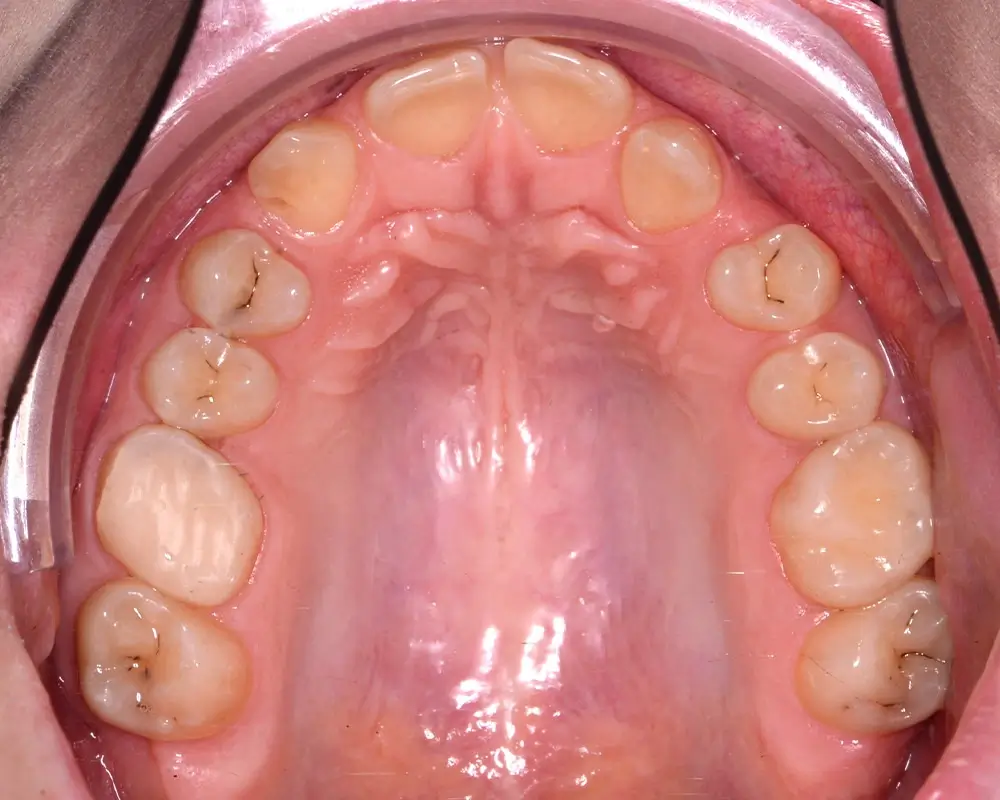

Кейс 8

Бажанова Ольга Валерьевна

Количество кап ВЧ 24

Количество кап НЧ 24

ДО